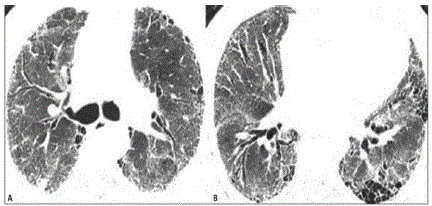

Você está diante de um paciente portador de fibrose pulmonar idiopática, última tomografia mostrada abaixo, com prognóstico reservado em relação à doença de base, familiares conscientes da situação. Diante do quadro de exacerbação aguda da doença, o que é melhor indicado?

enunciado 1853068-1